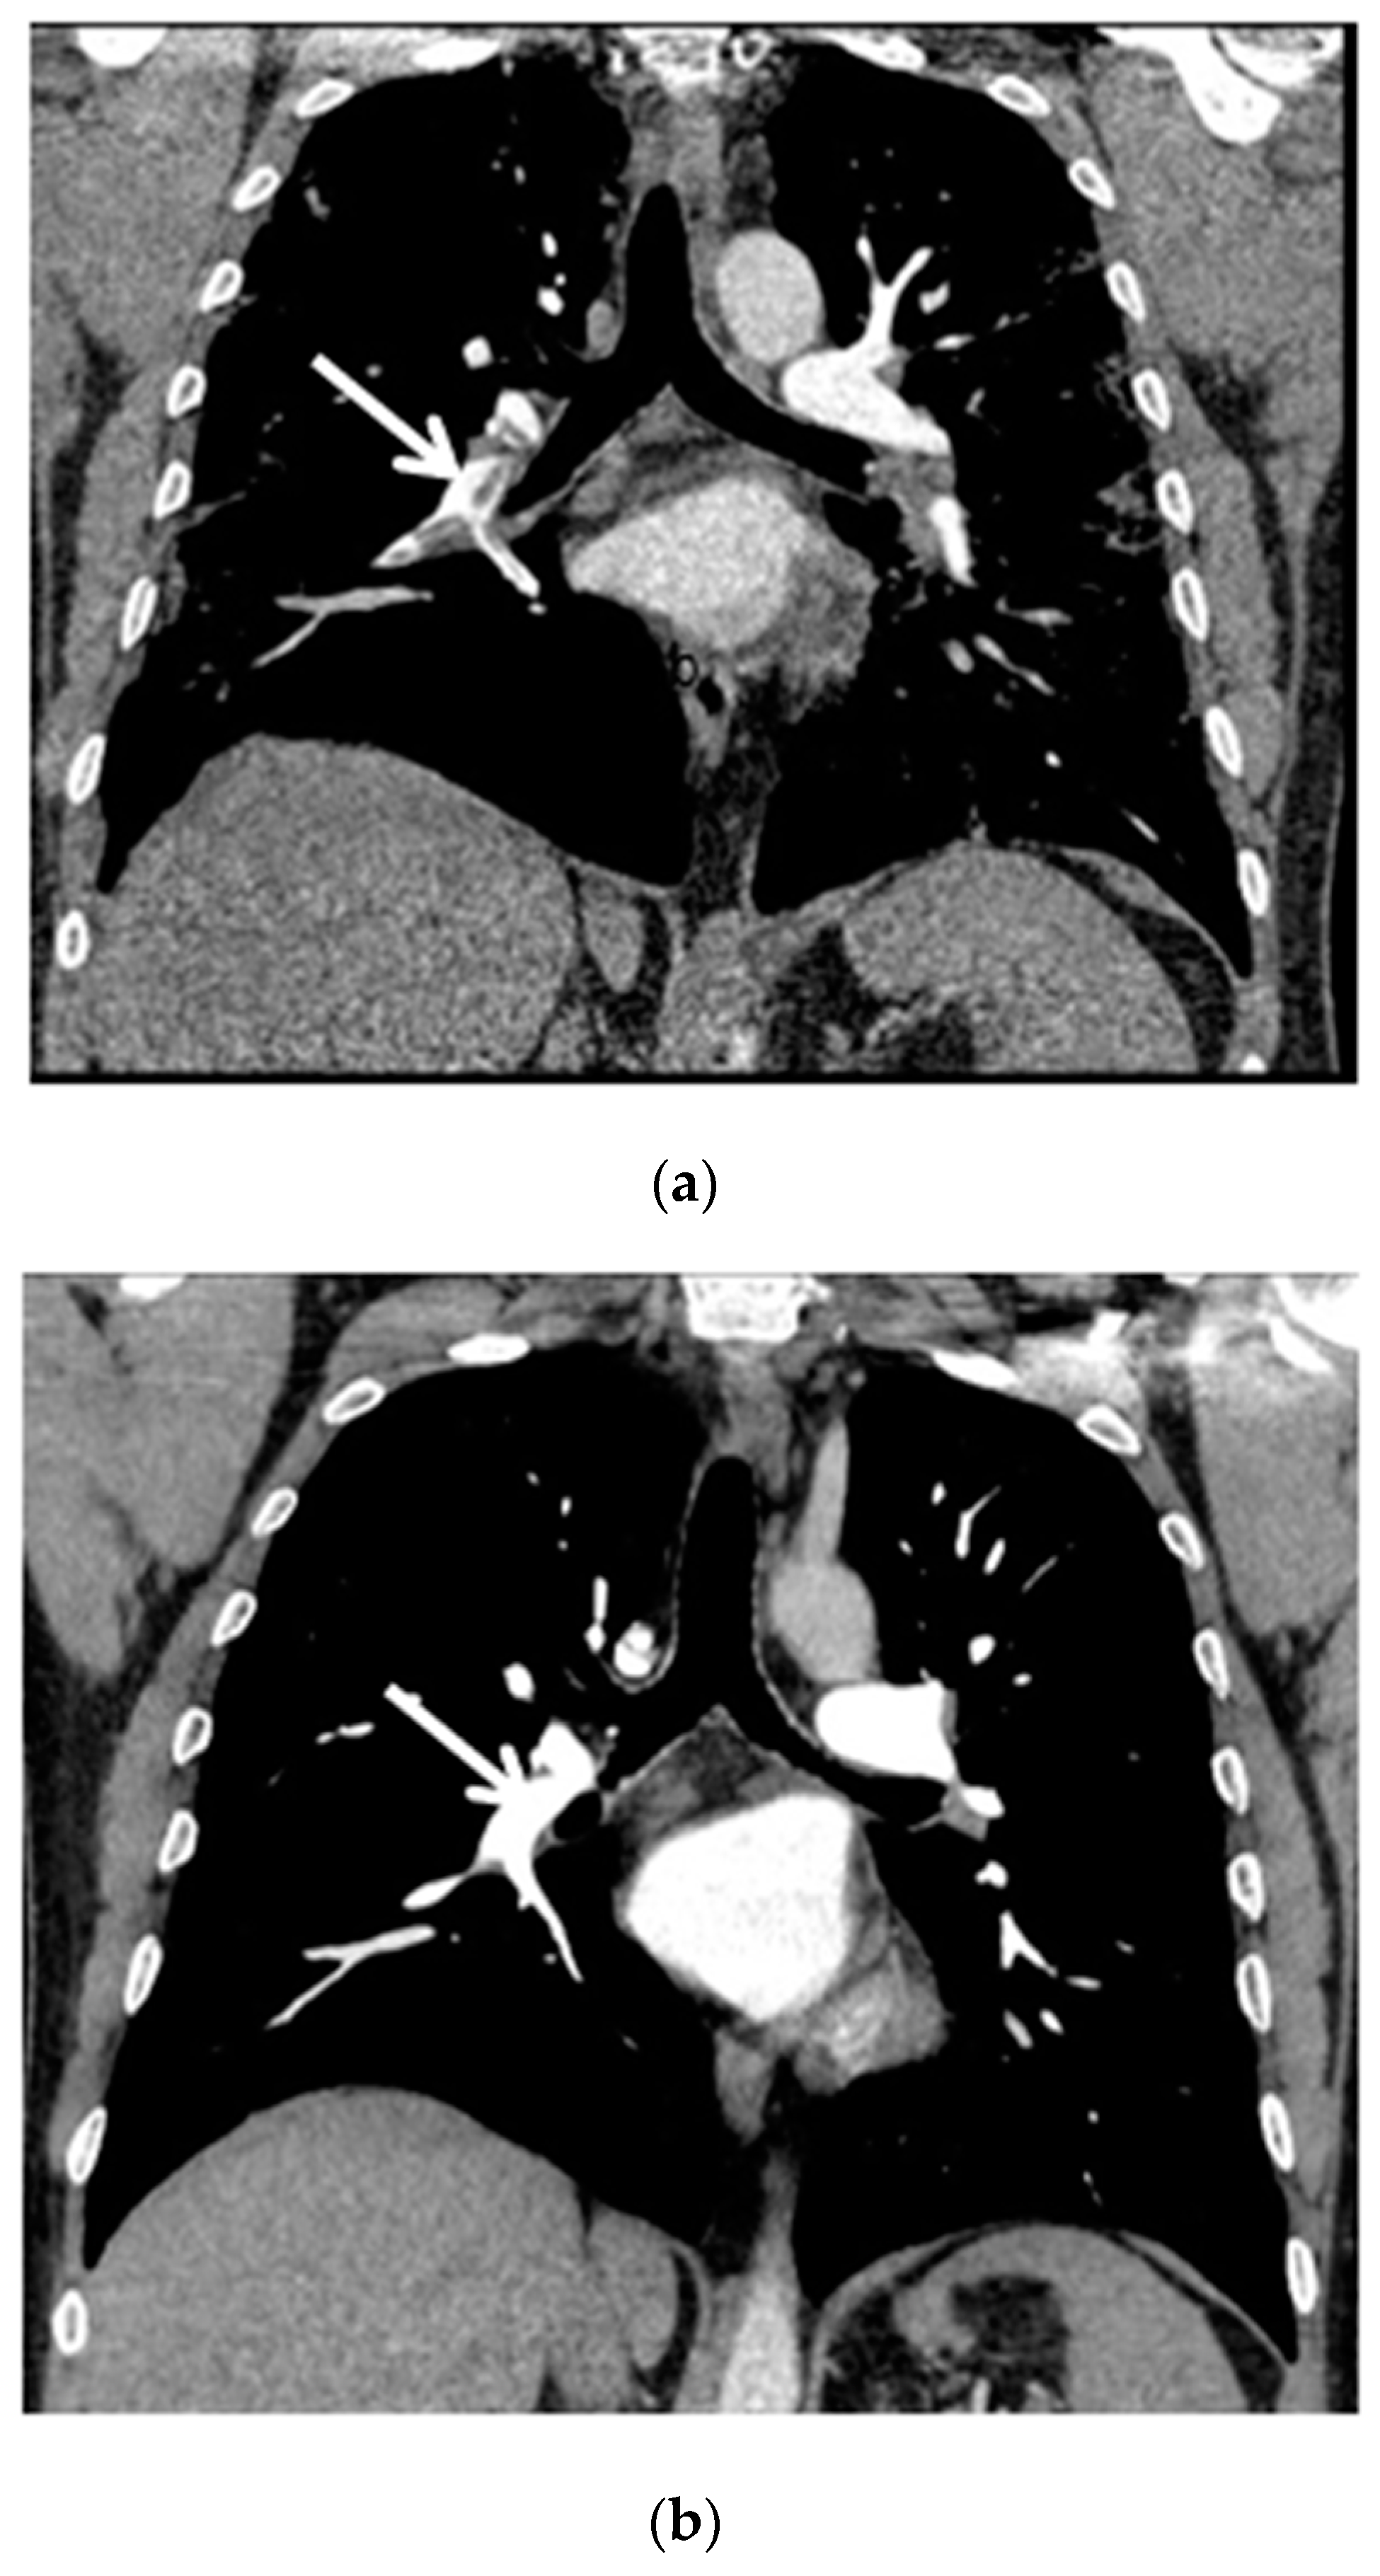

The control chest X-ray showed an almost complete regression of parenchymal lung disease, compared to the initial examination (Figure 1b). A follow-up CTPA showed complete regression of pulmonary embolism (Figure 2a,b); moreover, significant regression of parenchymal lung disease was found (Figure 3a,b).

Figure 2.

(a) Chest CT scan (mediastinal window, coronal view) shows pulmonary embolism that affects the right pulmonary artery, lobar arteries of the right lower and upper lobes and interlobar pulmonary artery (white arrow); (b) Chest CT scan after six months of follow-up shows complete resolution of thrombosis (white arrow).